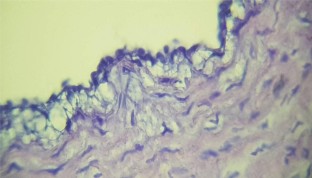

Fig. 3